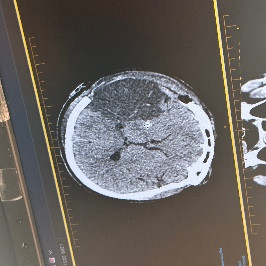

Stroke mumma